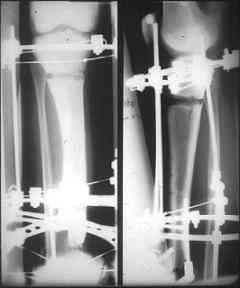

отделяемое. #1;#2. Стержневой апп. снят, наложен апп. Илизарова, дренажно-ирригационная система промывки раны. #3; #4. После стихания инфекции,

аппаратом постепенно создана рекурвация для сближения контактов мышц (сухожилий) передней группы голени. #5;#6. Наложен шов на сухожлилия М.

Tibialis anterior и M extensor digitorum L. Одновременно компактотомия костей голени в В/3 для замешение дефекта костей. #7;#8. Постепенно